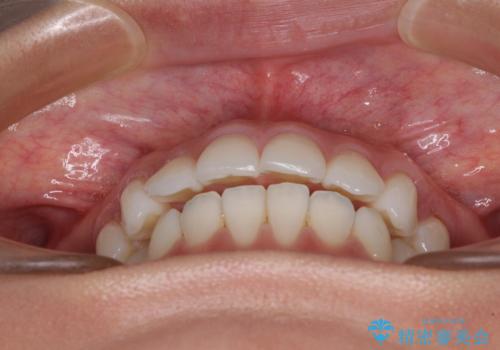

【モニター】インビザラインで口を閉じやすく

- 前に出ている上顎前歯が気になるとのことで来院された患者様です。

インビザラインを用い、IPR(歯と歯の間を削る)と歯列全体を後方に移動させることで、可能な限り前歯の突出感を改善することとしました。

元々の歯列も整っており、横顔の印象の出っ歯ではなかったため、仕上がりに満足できない可能性があると心配しておりましたが、口が閉じやすくなり、患者様には大変満足していただきました。